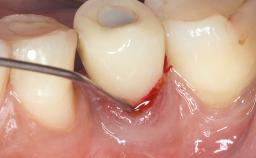

Treatment of Peri-Implant Mucositis at a Zirconia Implant

Recent clinical studies, most with short-to-medium term observation periods, have reported on the favorable clinical performance of zirconia implants in terms of survival rates, clinical, and radiographic outcomes (Roehling and coworkers 2016; Roehling and coworkers 2017; Rodriguez and coworkers 2018; Lorenz and coworkers 2019). Nonetheless, a rather high incidence of peri-implant disease at zirconia implants (39% of implants) was noted throughout a two-year period, highlighting the need for treatment protocols of peri-implant diseases at zirconia implants (Becker and coworkers 2017).